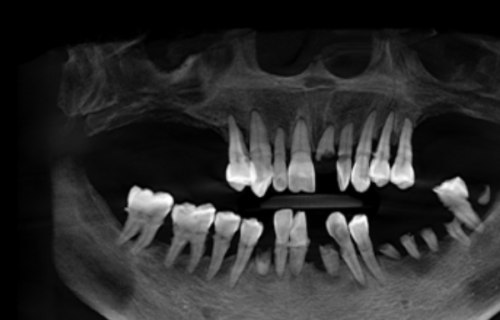

禁忌人群:虽然隐形种植牙有特别多优点,但并不是所有人都适合。患有重度的心血管疾病、未控制的糖尿病、血系统疾病等全身性疾病的患者,可能不适合进行隐形种植牙手术。因为这些疾病可能会影响手术的安心性和术后的修复成效。此外,牙槽骨重度吸收、口腔卫生状况较差的患者也需要在治疗改善后,再考虑是否适合隐形种植牙。